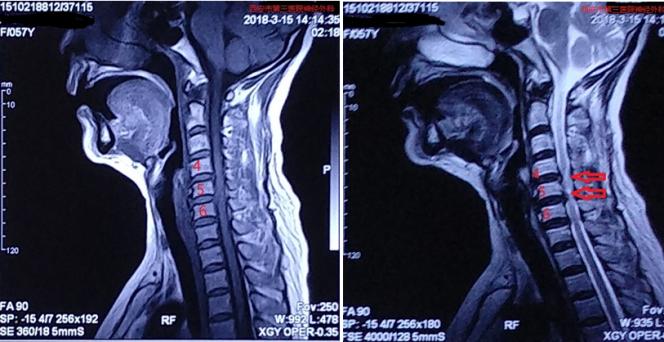

术前颈椎MRI

矢状位MRI提示颈4/5、5/6椎间盘突出,后方脊髓受压变性

轴位MRI提示颈4/5中央型、5/6外侧型椎间盘突出,压迫后方脊髓组织